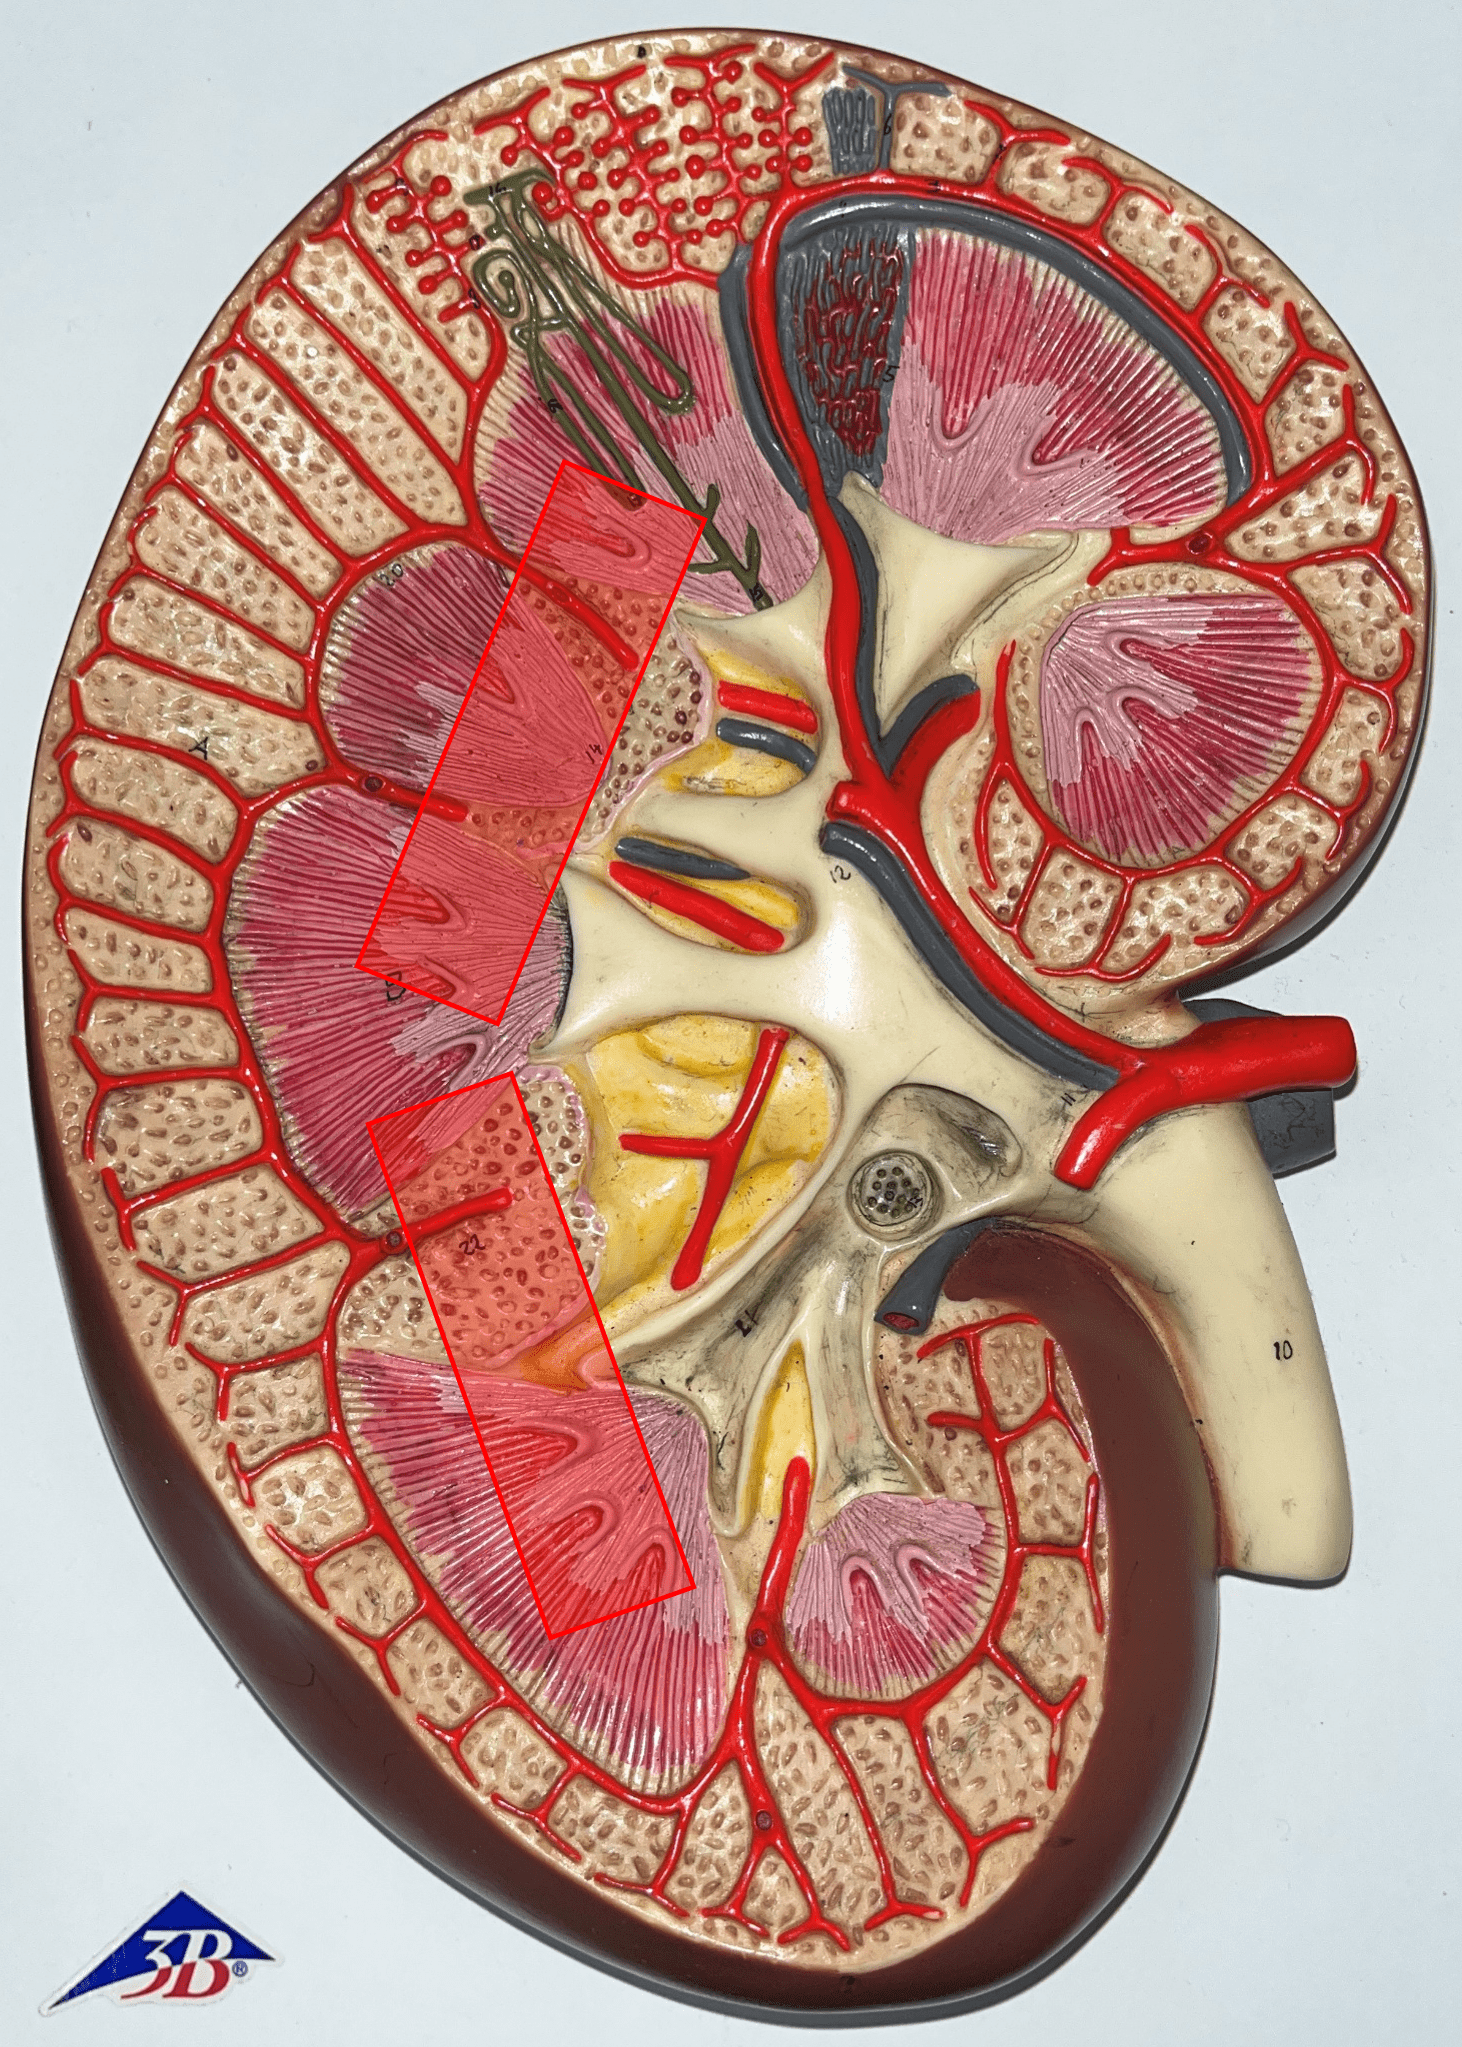

renal medulla

• The middlemost region of the internal kidney.

• Deep to the renal cortex and superficial to the renal pelvis.

• Contains triangular renal pyramids.

• Appears striated due to the presence of tubules and ducts.

• Deep to the renal cortex and superficial to the renal pelvis.

• Contains triangular renal pyramids.

• Appears striated due to the presence of tubules and ducts.

renal pyramid

• A triangular structure found in the renal medulla.

• The base faces the renal cortex.

• The renal papilla (apex) faces the renal pelvis.

• The base faces the renal cortex.

• The renal papilla (apex) faces the renal pelvis.

renal column

An area of granular tissue (similar to the cortex) between renal pyramids.

interlobar artery

• Extends between the renal pyramids.

• Branches of a segmental a.

• Branches into smaller arcuate aa.

• Branches of a segmental a.

• Branches into smaller arcuate aa.